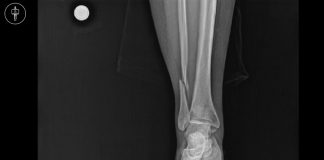

Cotton Kırığı Olgu Sunumu

43 yaşında kadın hasta, ev içi merdivenden elinde eşya taşıyarak yukarı doğru çıkarken üçüncü basamakta ayağı kaymış ve sol ayak bileği inversiyonda kalacak şekilde...